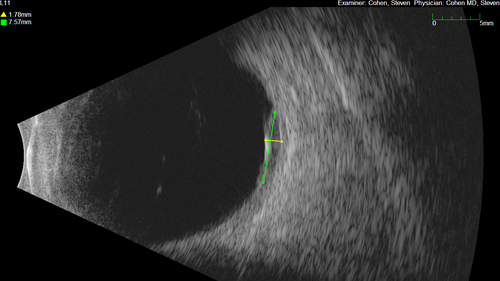

Serous Macular Detachment from Small Choroidal Melanoma

72 year old female misdiagnosed as CSR who had small choroidal melanoms.